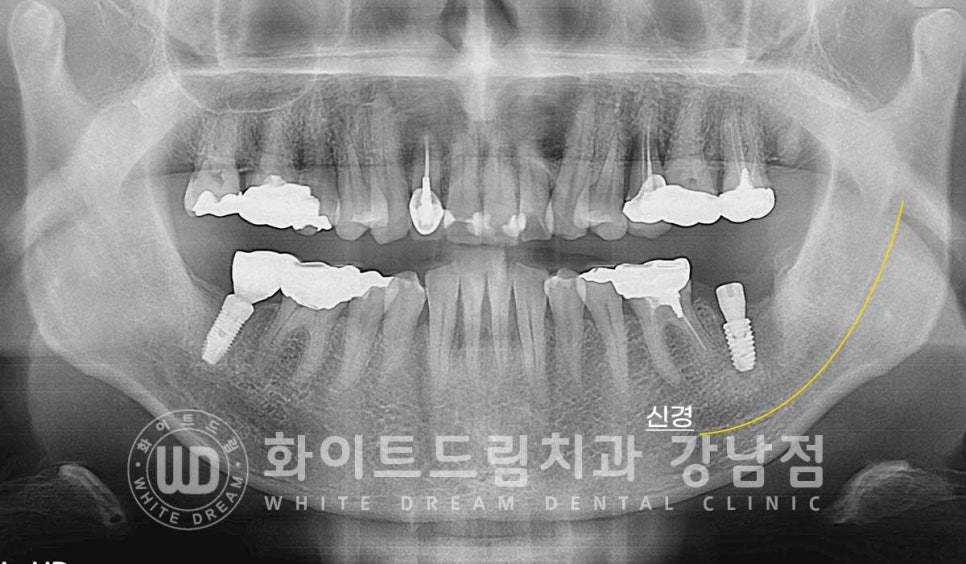

3개월의 임플란트가 새로운 뼈와 유착되는 시간을 가지면서

정상적으로 회복되고 있음을 확인한 후에 이제 임플란트 최종 보철 제작에 들어가게 됩니다.

총 치료 기간은 23.08.14 - 24.02.03으로 약 6개월 정도의

치료 기간이 소요되었습니다.

▲ 이식재가 새로운 뼈로 생성되었고 임플란트와 단단하게 결합된 것이 확인됩니다.

동일 인물이며 동일 환경에서 촬영되었습니다.

강남역 임플란트재수술 치과 / 치료 기간 : 23.08.14 - 24.02.03